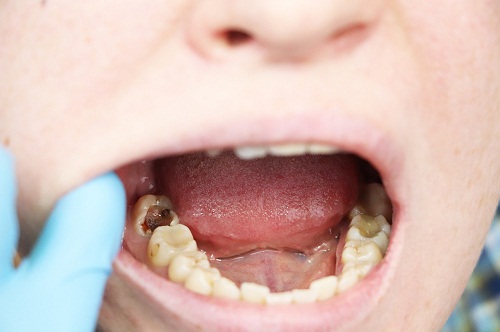

蛀牙(齲齒)是一種進行性疾病。早期症狀可能不明顯,但如果不及時幹預,齲壞會從牙釉質深入牙本質,從而可能波及牙髓,導致疼痛、感染甚至牙齒喪失。補牙是目前治療早期和中期蛀牙較為直接有效的方法。

其核心在於完全清除腐壞的牙體組織,並使用生物相容性好的材料進行填充修複,以恢複牙齒的外形和咀嚼功能,阻止齲病進一步發展。因此,一旦發現牙齒上有黑點、黑線或對冷熱刺激敏感,建議盡快進行口腔檢查。